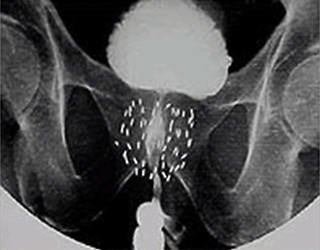

密封小線源療法とは何ですか?

小さな線源を前立腺内に挿入し、前立腺内のがん病巣へ線源から放射線を照射する放射線治療です。